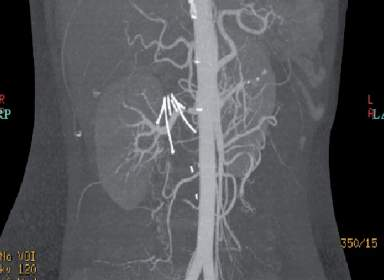

IVC filter

device placed into IVC percutaneously, just below the renal veins, to trap any lower extremity venous thromboemboli before they reach the heart and lungs

percutaneous placement is through common femoral or jugular vein » doesn’t significantly obstruct blood flow

indicated when a pt. has known lower extremity venous thrombosis, or at risk for redeveloping thrombosis, and anticoagulation therapy is contraindicated

most devices consist of thin metal struts joined at one end to form the shape of a cone

sono findings:

should be situated below renal veins

metal struts appear as echogenic lines

should have pulsatile flow in VC above the filter, and phasic flow below

What can you conclude from this image of an IVC filter?

there’s IVC perforation from the filter

filter strut extends outside IVC

What is the purpose of the device imaged below? Â

(This image shows vascular filling through the arteries only.)

offer alternative treatment for when antocoagulant therapy is contraindicated

prevent pulmonary embolism

break up deep venous thrombosis emboli